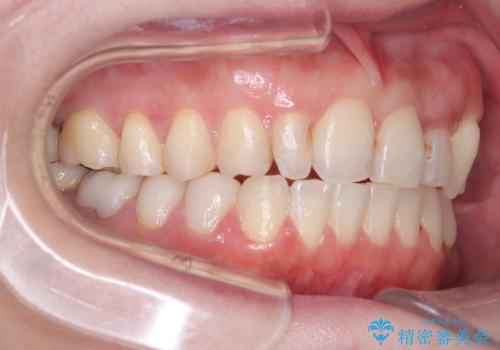

まず、計画通り左上4番を抜歯し、そのスペースを利用して八重歯を徐々に正しい位置へと移動させました。ワイヤー矯正特有の「歯を細かく、確実に動かす力」を最大限に活用し、歯根の向きまで丁寧に調整。

治療が進むにつれ、突出していた八重歯がスムーズに列に収まり、凹凸がなくなったことで、以前よりもブラッシングがしやすく清潔な口腔環境が整いました。治療完了後、長年のコンプレックスから解放された患者様の笑顔は非常に明るく、40代からでも遅くない「大人の矯正」の大きなメリットを実感していただける症例となりました。